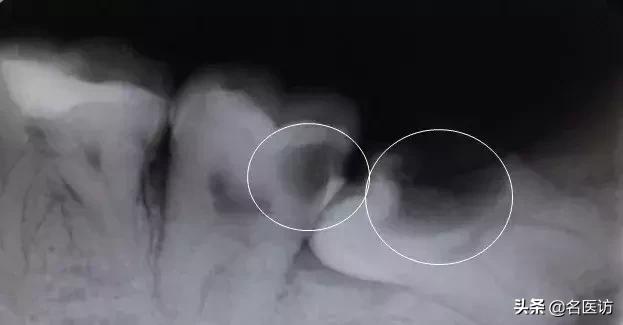

智齿以及前面的第二磨牙龋坏

第二磨牙与智齿之间牙槽骨吸收